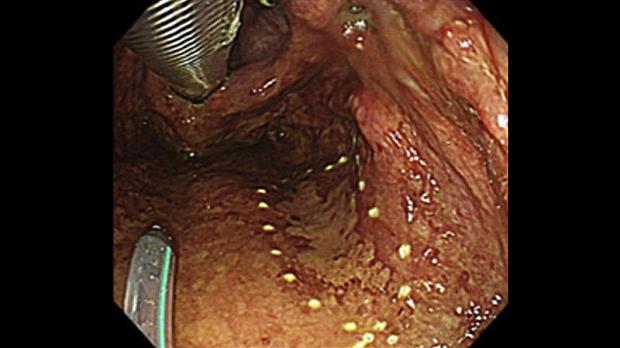

Обнаружение поверхностного рака глотки становится все более распространенным благодаря таким достижениям, как узкополосная визуализация и визуализация с использованием синего лазера.1,2 Эндоскопическая диссекция подслизистой оболочки (ESD) при поверхностном раке глотки полезна в качестве минимально инвазивного лечения.3,4Однако поражения задней стенки ротоглотки обычно трудно удалить с помощью обычного трансорального эндоскопа, поскольку они перпендикулярны мышечному слою, а субэпителиальный слой в этом месте довольно узкий ( рис. 1 ). В таких случаях полезен трансназальный эндоскоп. Здесь мы сообщаем об ЭСД ротоглотки с помощью трансназального эндоскопа.

Пациент был 71-летним мужчиной, у которого в анамнезе был ESD пищевода и глотки для поверхностной плоскоклеточной карциномы. При контрольной эндоскопии выявлено красноватое пятно на задней стенке ротоглотки. При узкополосном увеличении изображения поражение можно было распознать как коричневатую область, а исследование биопсии выявило плоскоклеточный рак. ЭСД проводился пациенту под общим наркозом в операционной.

Время процедуры от разреза до резекции составило 40 минут. Патологическое исследование выявило плоскоклеточный рак in situ размером 25 × 14 мм, край отрицательный. Жидкое питание было начато на третий день после ESD, и пациент был выписан из нашей больницы через 9 дней после ESD. Через два месяца после ESD язва ESD полностью зажила.